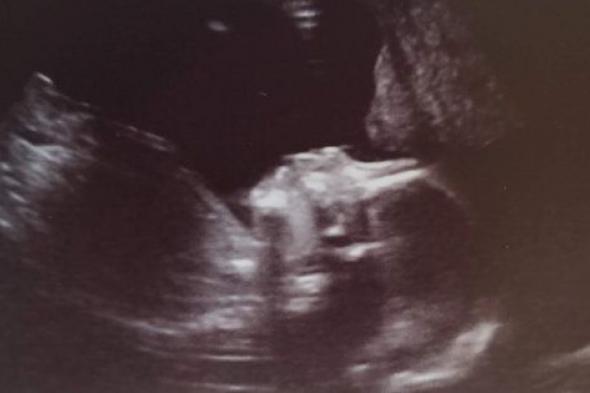

Mi hija de 20 semanas.Nicholas Mizera

Ya había visto la primera ecografía de nuestro bebé, aún de sexo desconocido, cuando solo tenía unas tiernas 12 semanas. Era una imagen difusa que ni se acercaba a resumir la enormidad del camino que nos precedía. Recordamos que nos admitimos el uno al otro que, pese a que teníamos pruebas palpables de que estaba sucediendo de verdad, casi nada de eso parecía real.